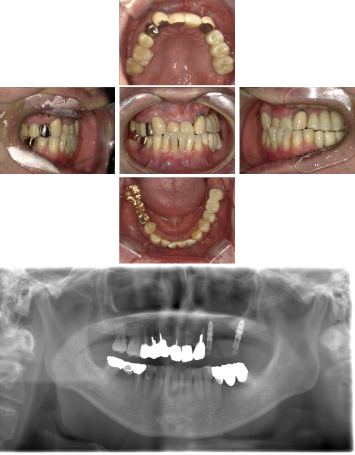

60代 女性 全顎 インプラント サイナスリフト等

| 年代・性別 | 60代・女性 |

| 主訴 | 上顎の入れ歯が割れた。リンゴやおかきを食べられるようになりたい。 |

| 部位 | 右上④3②・左上②3④5⑥のブリッジ |

| 治療期間 | 2年 |

| 費用 | ¥2,447,500(税込) |

| 副作用・リスク |

|